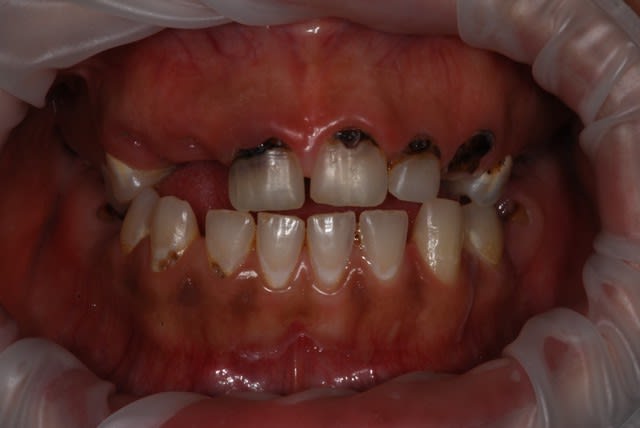

Vu cette semaine, en 2 jours,

3 cas d'allergie à la brosse à dents...